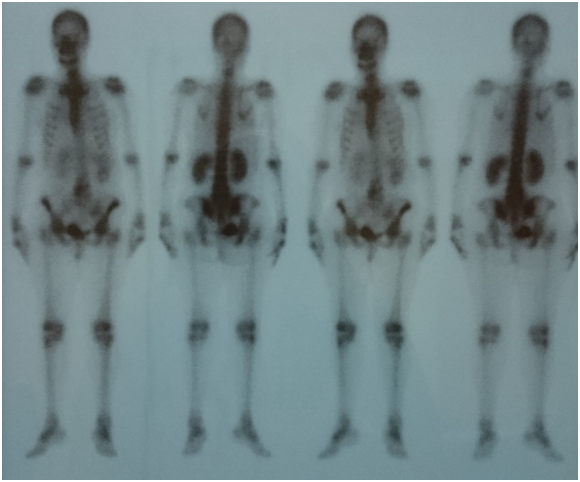

As patient still having backache, Magnetic Resonance Imaging (MRI) lumbo-sacral region was done to evaluate any deterioration in the disc prolapse state. Paraspinal mass was illustrated in MRI assessment (Figure 1) suggestive of metastatic lesion. So, bone scan was ordered to evaluate the nature of the lesion, and the results revealed neoplastic lesion involving L4 (Figure 2).

Figure 1 Non contrast MRI lumbosacral spine, bone marrow of L4 and L5 is seen replaced by abnormal SI in form of low SI on T1 and high SI on both T2 and STIR images?? Mostly metastatic lesion.